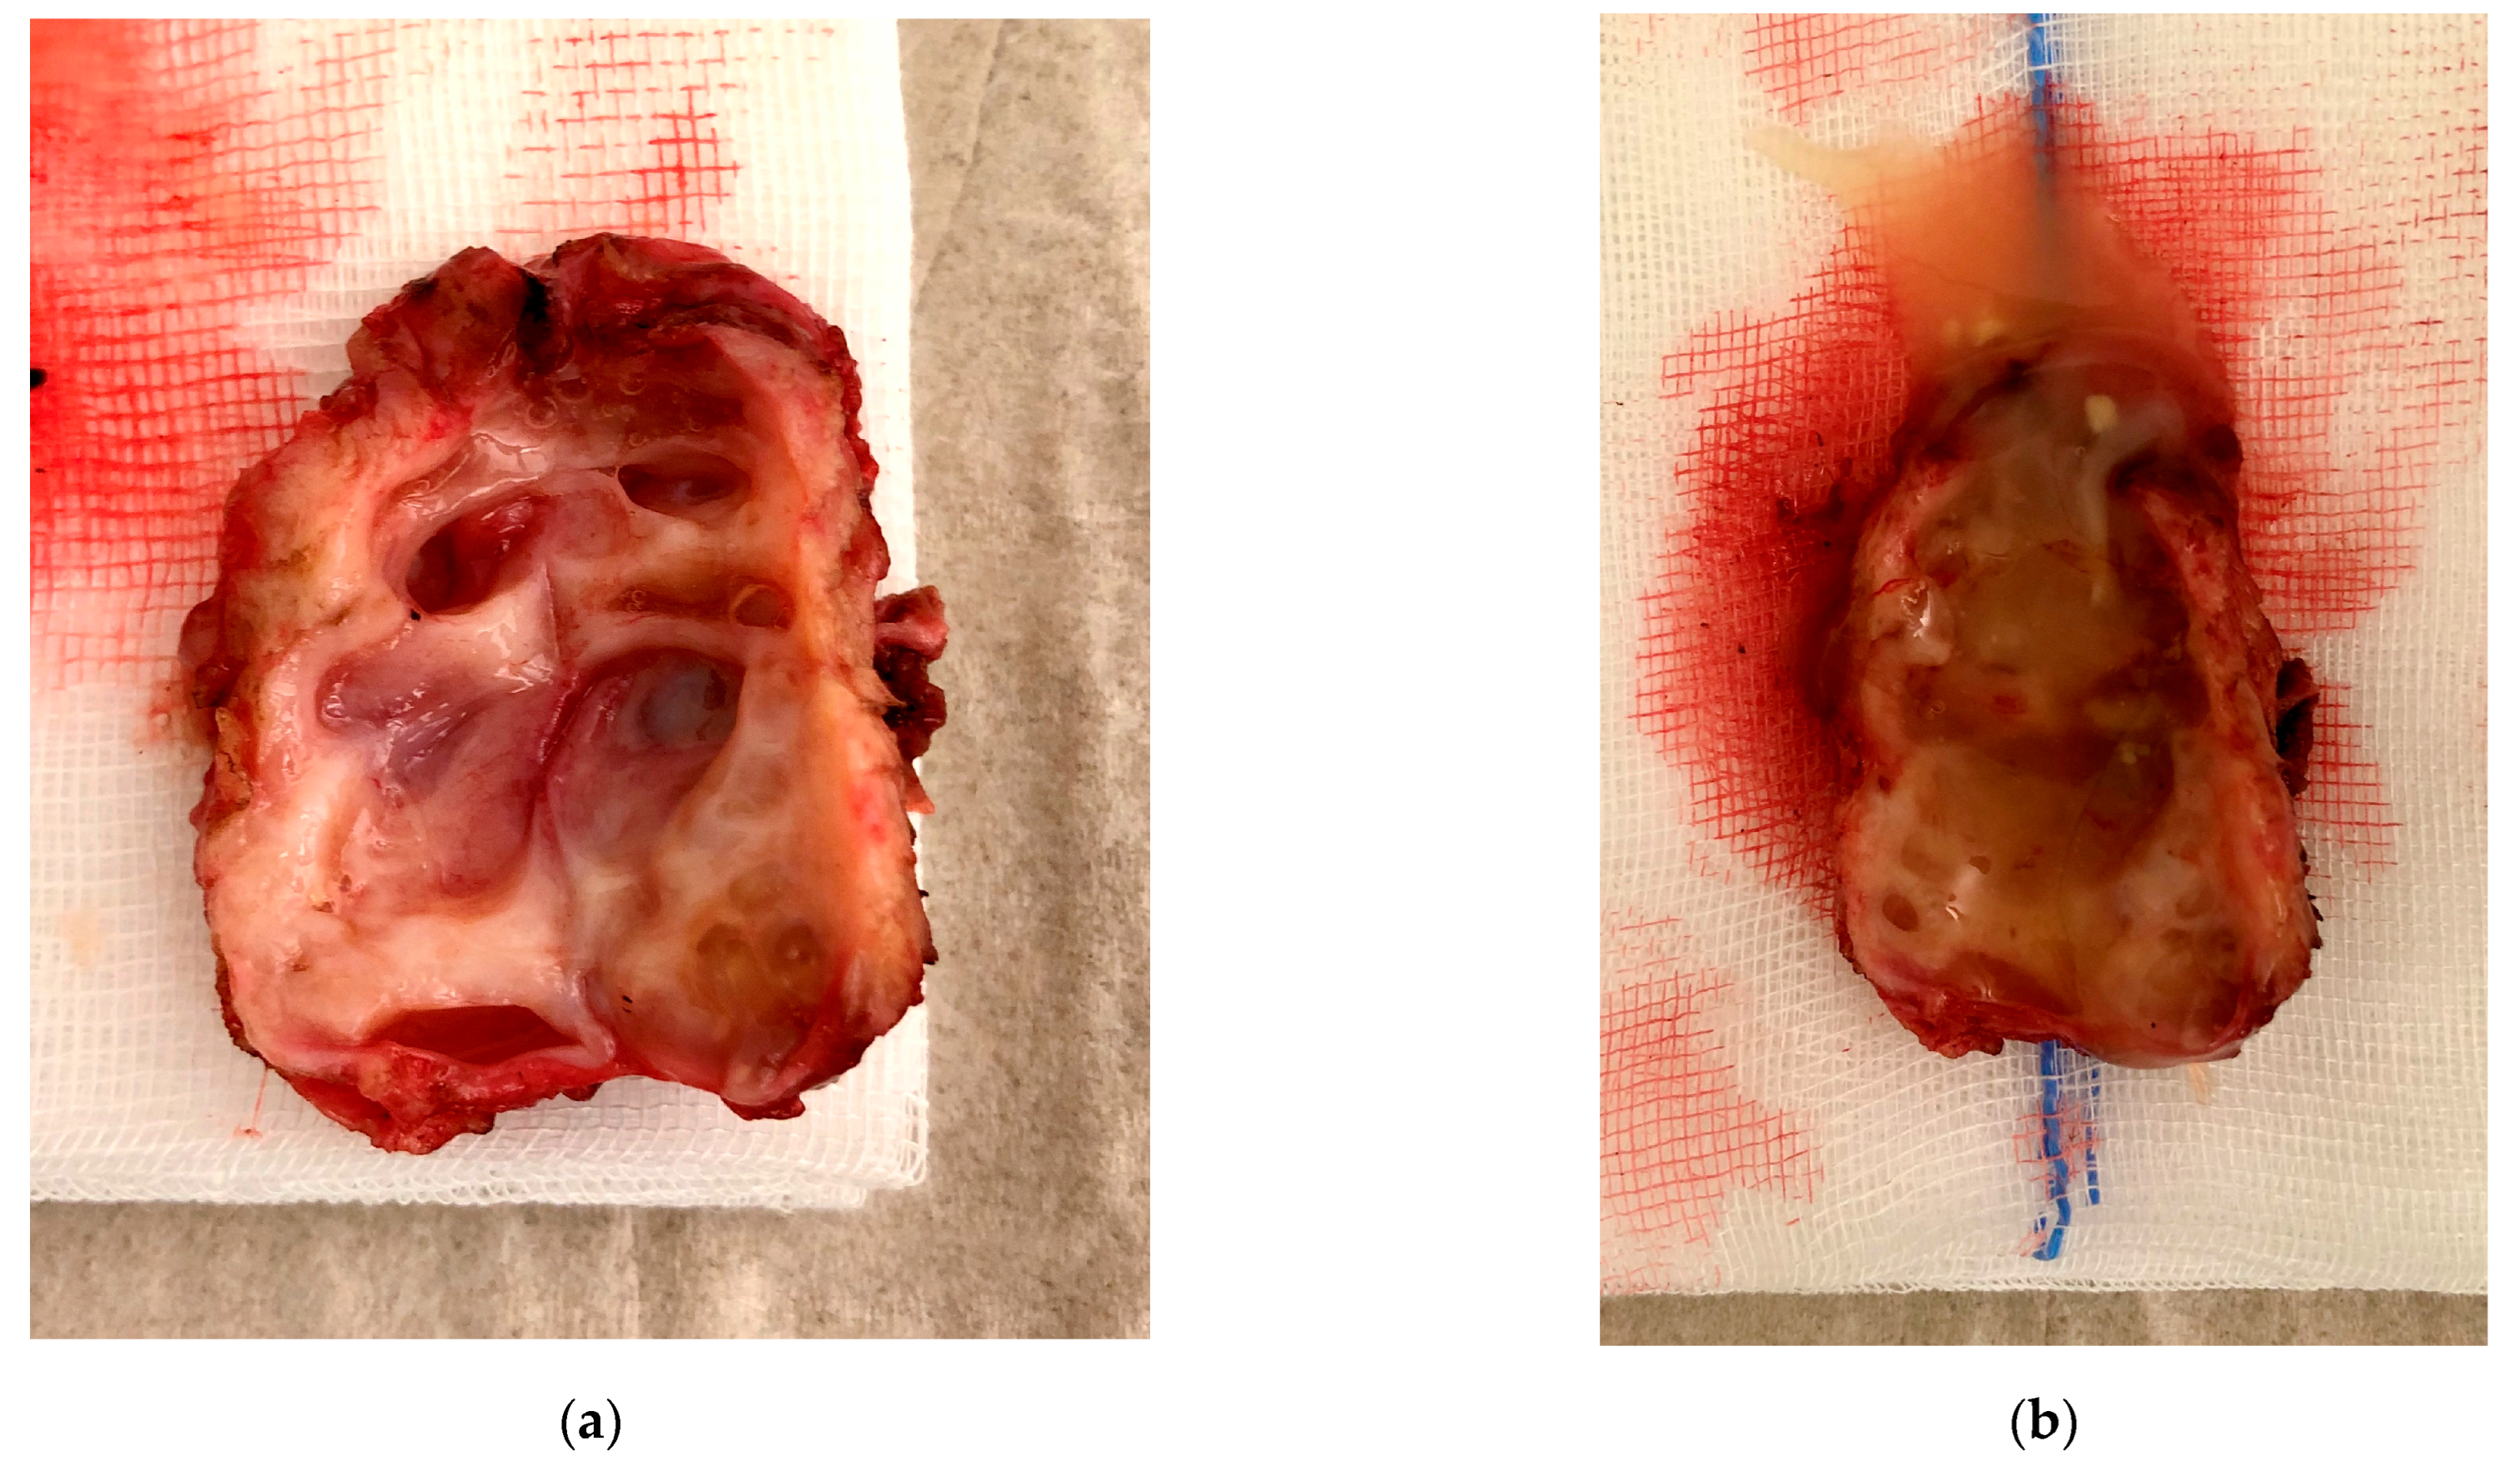

3.3. Case 3—Niche Placentation Failure—Emergency Hysterectomy

3.4. Case 4—Niche Pregnancy—Laparoscopic Subtotal Hysterectomy

3.5. Case 5—Niche Pregnancy—Laparoscopic Resection and Repair

3.6. Case 6—Niche Pregnancy—Combined Hysteroscopic and Laparoscopic Treatment

3.7. Case 7—Symptomatic Niche—Laparoscopic Treatment

3.8. Case 8—Symptomatic Niche—Laparoscopic Treatment

3.9. Case 9 —Symptomatic Isthmozele—Laparoscopic Treatment

| Case 1 | 34 | 2 | Bleeding disorder, dysuria, dyspareunia | Laparoscopic ICG niche detection and resection | Adenomyosis |

| Case 2 | 31 | 2 | Niche pregnancy, 6 weeks after IVF Pelvic pain and vaginal bleeding | Hysteroscopic resection, second look laparoscopy with scar resection and suture | Chorionic villi, decidua, adenomyosis |

| Case 3 | 40 | 1 | Niche pregnancy with placenta increta and uterine rupture, 13 weeks | Emergency hysterectomy | Placenta praevia, Placenta increta, uterine fibroids, no adenomyosis |

| Case 4 | 39 | 2 | Niche pregnancy, 8 weeks, dysmenorrhea, vaginal bleeding | Subtotal hysterectomy with scar resection (patients wish) | Chorionic villi, decidua, adenomyosis |

| Case 5 | 40 | 3 | Niche pregnancy, 7 weeks of gestation | Laparoscopic resection and repair | Chorionic villi, decidua, no adenomyosis |

| Case 6 | 43 | 1 | Niche pregnancy, 9 weeks, IVF | Hysteroscopic resection second look laparoscopy with resection and repair | Chorionic villi, decidua, no adenomyosis |

| Case 7 | 27 | 1 | Dysmenorrhea and pelvic pain, subfertility | Laparoscopic niche resection and suturing | Adenomyosis |

| Case 8 | 31 | 1 | Bleeding disorder, dysmenorrhea | Laparoscopic niche repair | Adenomyosis |

| Case 9 | 36 | 2 | Large symptomatic isthmocele | Laparoscopic resection and repair | No adenomyosis |